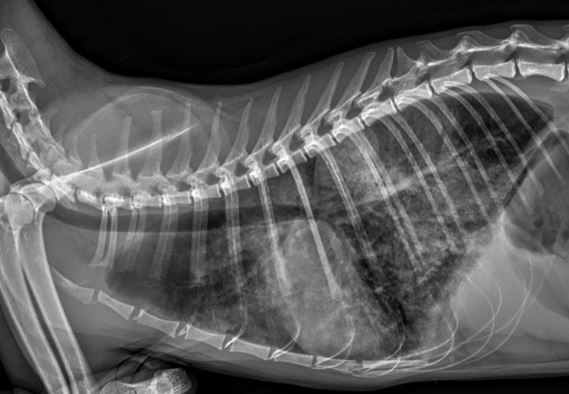

Stage D 강아지 심장병심장병 D단계 포메라니안, 이뇨제 내성으로

반응 저하를 극복한 맞춤 치료 케이스 -

폐성고혈압 우심부전갑작스러운 식욕부진과 켁켁거림,

폐성고혈압으로 인한 우심부전이었습니다. -

호흡곤란 고양이 비대성 심근병증개구호흡과 저체온 증상으로 응급내원!

유전적 요인의심장병, 혈전 예방치료까지